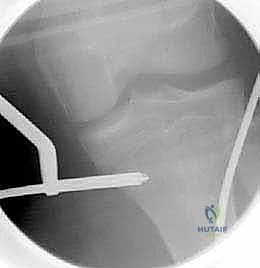

* الرد المغلق (Closed Reduction): إذا كان العظم منحرفاً قليلاً، يقوم الدكتور هطيف بإعادة العظم إلى مكانه الصحيح يدوياً تحت تأثير التخدير العام أو الموضعي، ثم يضع الجبس.

- استخدام جهاز الأشعة القوسي (C-Arm Fluoroscopy): يُستخدم هذا الجهاز المتطور طوال العملية لتوفير صور أشعة حية ومباشرة، مما يسمح للدكتور هطيف برؤية العظم من الداخل دون الحاجة لشقوق جراحية كبيرة.

- تمرير المسامير والتثبيت: يتم إدخال المسامير المرنة بمهارة فائقة داخل تجويف العظم وتوجيهها لتتجاوز منطقة الكسر، مما يعيد العظم إلى استقامته الطبيعية ويثبته بقوة.